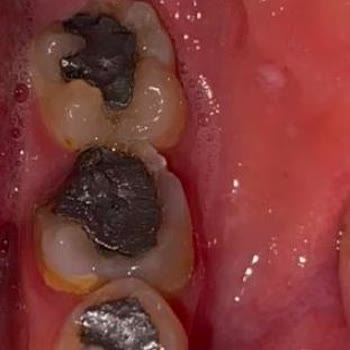

İzmir Alsancak ADSM’de yaklaşık 1,5 yıl önce DT. G***** S******* tarafından aynı gün içinde, toplamda sadece 20 dakika gibi kısa bir sürede bir kanal tedavisi ve iki dolgu işlemi yapıldı. Tıbbi standartlara göre çok daha uzun sürmesi gereken bu işlemlerin bu kadar süratle bitirilmesi, 1,5 yıldır sür...